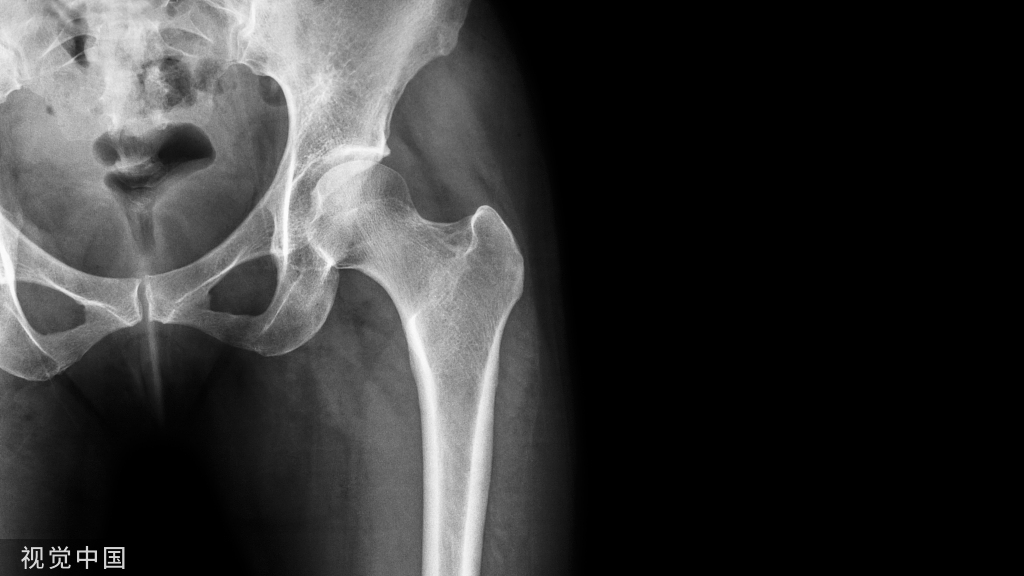

初次就诊2年后:

不错嘛,在工作、生活没耽误的前提下,病人偶尔来医院复查或治疗,也没有想象中的那么不便。初次就诊近3年复查:

这股骨头杠杠的!